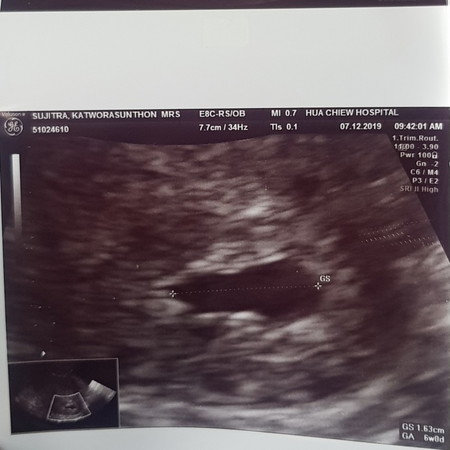

วันนี้ไปหาหมอ หมอซาวด์แล้วบอกว่าเด็กฟ่อไปแล้ว เป็นท้องลม เสียใจมากๆ คะ 10w5d